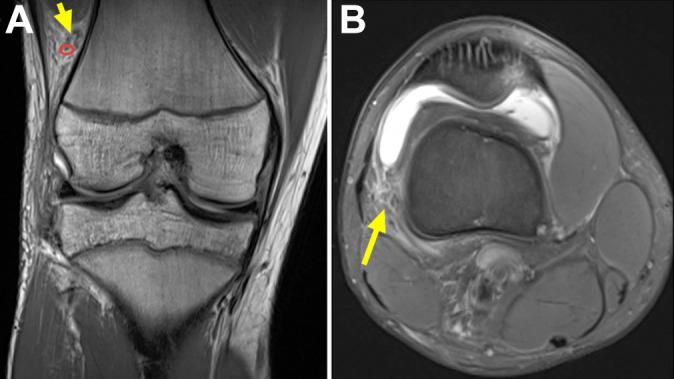

Skeletally immature patients with an acute ACL tear confirmed using MRI within 90 days of injury were assessed. Two fellowship-trained musculoskeletal radiologists independently interpreted each MRI scan twice. KF injury was first assessed using the Van Dyck scheme (grade 0, normal; grade 1, periligamentous; grade 2, partial tear; and grade 3, complete tear). MRI scans were then reviewed again using the KF injury criteria proposed by Batty. Discrepancies in KF injury schemes were adjudicated by a third musculoskeletal radiologist. Interrater agreement for both methods was determined using Cohen κ.

方法

对在受伤90天内通过MRI确诊为急性ACL撕裂的骨骼未成熟患者进行评估。两名接受过专科培训的肌肉骨骼放射科医生分别对每次MRI扫描进行两次独立解读。首先使用范戴克方案评估KF损伤(0级,正常;1级,韧带周围;2级,部分撕裂;3级,完全撕裂)。然后使用巴蒂提出的KF损伤标准再次审查MRI扫描。KF损伤方案的差异由第三位肌肉骨骼放射科医生进行判定。使用科恩κ系数确定两种方法的评分者间一致性。